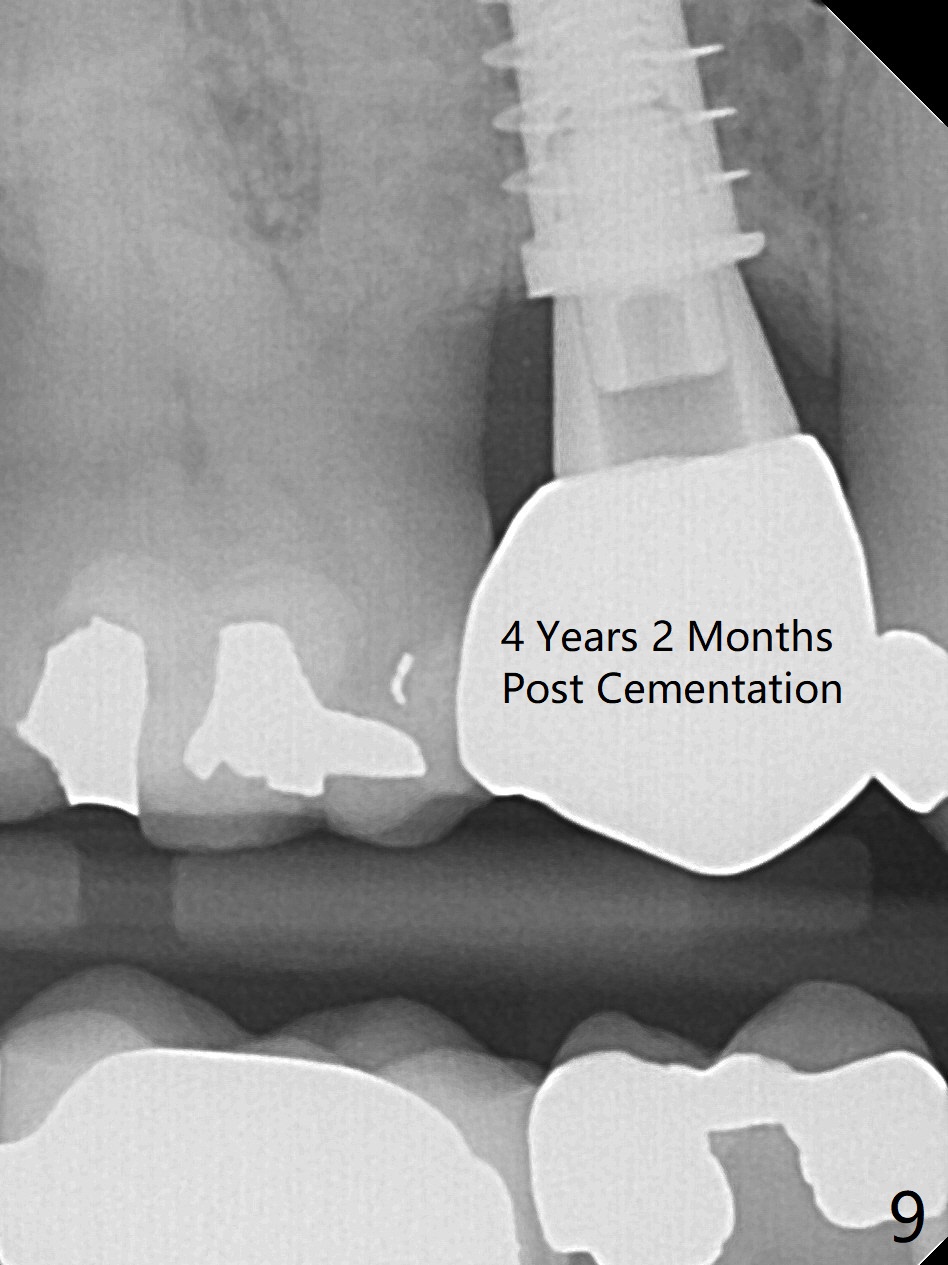

To prevent sinus lift related sinusitis, a shorter implant is going to be placed (Fig.1), approximately 2 mm beyond the apex. Following extraction, the buccal plate (Fig.3a (coronal section): B) is not only ~ 2 mm shorter than the palatal one (P), but also thinner. Since the bone density of the palatal plate is higher, without osteotomy an implant is less likely placed in the middle of the socket (S (Fig.1); Fig.3b) than buccal (Fig.3c). Therefore drills are used to form osteotomy in the apical 1/3 of the palatal slope (Fig.3d (red arrow); SM: sinus membrane). When 3.3 mm Magic Drill (MD) is in place (Fig.2), the distal surface of the sinus septum is perforated without air leakage. Demineralized allograft (.0125-.085) is placed for sinus lift (Fig.4 *) prior to placement of 4.5x11 mm implant with ~ 30 Ncm. The implant is slightly buccal to the ideal position indicated in Fig.3e (curved blue line: sinus lift). A 4.5x4(2) mm pair abutment is placed for an immediate provisional to hold mineralized allograft in the remaining socket gaps (Fig.4 arrowheads, .5-1.5 mm). A 9 mm implant may avoid sinus floor perforation on the distal slope of the 2nd premolar. The osteotomy should have been established initially as mesial as possible. In fact the patient has nasal hemorrhage while sneezing for the first 2 days postop. Although he complains of pain buccal to the implant, the gingiva appears to heal 7 days postop (Fig.5). The distobuccal papilla appears to be displaced somewhat. Raising mucoperiosteal flap is most likely associated with postop pain and esthetic compromise. The implant appears to have osteointegrated 5 months postop (Fig.6). A 4.5 mmx15° 3 mm cuff angled abutment is placed for final restoration. The distolingual portion of the implant is supported by the regenerated bone 3 years post cementation (Fig.7,8). There is no bone loss 4 years 2 months post cementation (Fig.9,10).